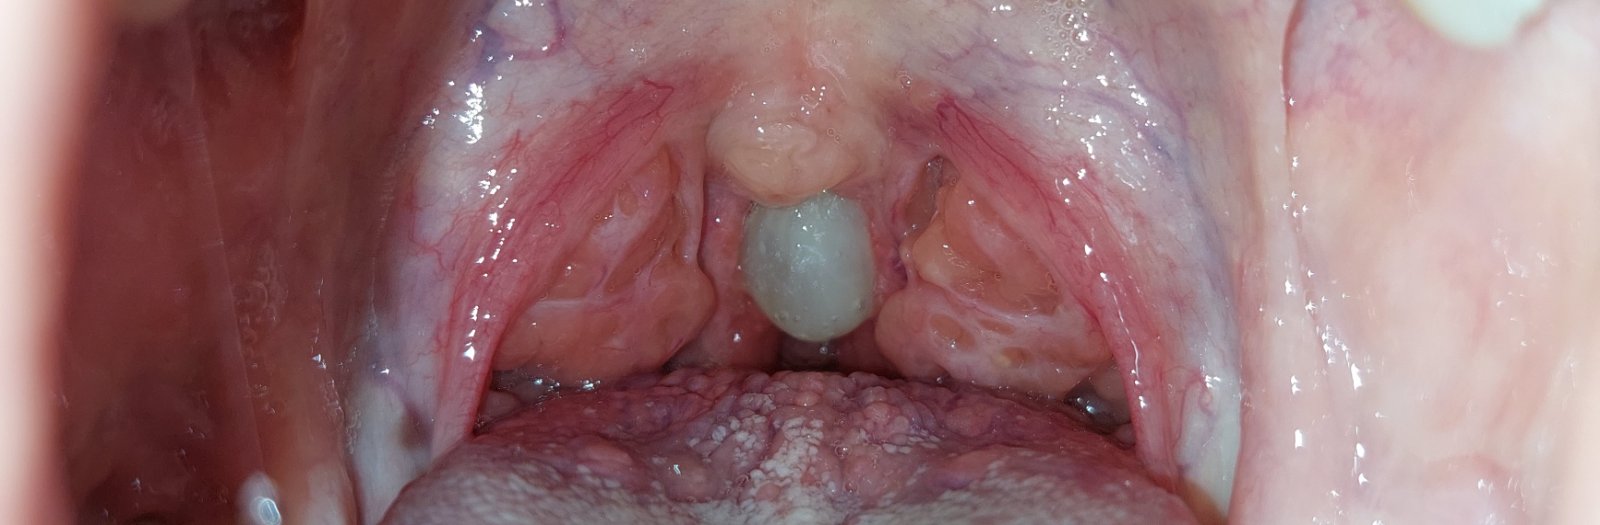

No teraz som si v hrdle všimla bielu guču, vyzerá to ako hlien, lebo to mám aj nižšie v hrdle také viac rozťahané... pridám sem aj nechutný obrázok 😔 prosím, nestretli ste sa niekto s niečím takým? A pomohlo vám niečo nato? Už som zúfalá, ťažko sa mi prehĺta, hrdlo ma stále bolí a tá hustá nádcha ide zo mňa stále, no vôbec sa mi to nezlepšuje. Dúfam, že to nebude niečo vážne, ako mi už dr.Google napovedal. Pôjdem určite k lekárovi. Náš obvodný ma má na háku a bez liekov ma pošle domov "veď to hrdlo nevyzerá tak zle".

@domuuska1 toto vyzera na nejaku dobru hnisavu anginu...kloktaj poriadne slanou vodou a urcite chod zas k lekarke..toto neprejde same

@kiki264 našťastie áno, ale s hlienmi je to u mňa vždy nadlho... celkovo som vtedy skúsila ešte konvičkovanie, sprej MAR do nosa, Sinupret kvapky, Kalobu, to kloktanie slanej vody a na viac si nespomínam. Skúšala som, čo som vtedy mohla ☹️ ten hlien na fotke sa mi podarilo vykašľať a každý deň som si to kontrolovala, či nemám znova. Bol to des. Prajem skoré uzdravenie aj vám 🙏